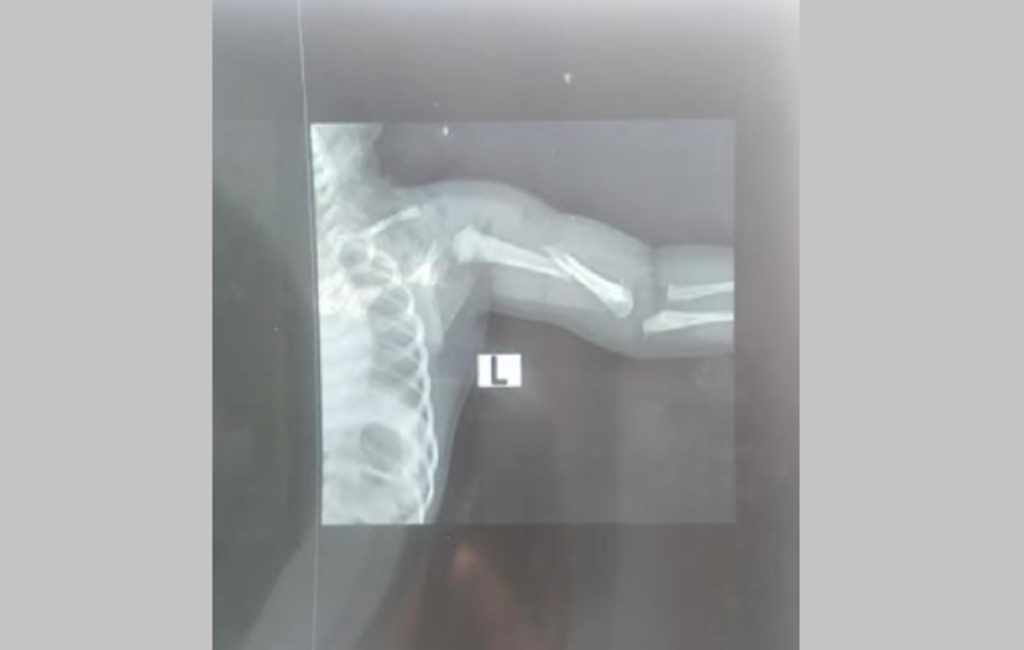

তখন এর কারণ জিজ্ঞাস করলে তারা বলেন, শিশুটির জন্মগত সমস্যা হয়েছে, তাকে হাসপাতালের চেয়ারম্যান ডা. আবু হামেদ বাবু দেখে বলতে পারবেন। এরপর ৮ মার্চ শিশুটির কান্না না থামলে ডা. আবু হামেদ বাবু তাকে দেখে জানান, শিশুটির জন্মের সময় হাত পিছনে ছিল তাই দুর্বলতা থেকে এমন হচ্ছে। তারপর তিনি এক্সরে করে জানান শিশুটির হাত ভাঙা। এই ঘটনায় হাসপাতালের পক্ষ থেকে কোনো ব্যবস্থা না নেয়ায় শিশুটির মামা মোস্তাকুল ইসলাম রোববার জেলা সিভিল সার্জন কার্যালয়ে লিখিত অভিযোগ দিয়েছেন।

ওই শিশুর নানি পারভীন বেগম জানান, নিয়মিত যে চিকিৎসকের তত্ত্বাবধানে ছিলাম তিনি আমাদের নবজাতকের সবকিছু নরমাল ছিল বলেন। কিন্তু সিজারের পর তারা শিশুটিকে আমাদের কাছে হাত ভাঙা অবস্থায় দেন।

অভিযোগকারী মোস্তাকুল ইসলাম বলেন, পেটের ভেতরে শিশুটির হাত পেছনে থাকায় সেটি ভেঙে গেছে বলেছেন ওই হাসপাতালের চিকিৎসক-নার্সরা। ওই সময় হাত ভেঙে গেলে শিশুটি জীবিত জন্ম নিতো না।

এ বিষয়ে জানতে চাইলে মোবাইলে অভিযুক্ত গাইনি চিকিৎসক তাসনুভা সাঈদ জানান, শিশুটির হাত ভেঙে যায়নি। মায়ের পেটে তার হাত পেছনে ছিল। জন্ম হওয়ার পর তার হাত ঝুলছিল।